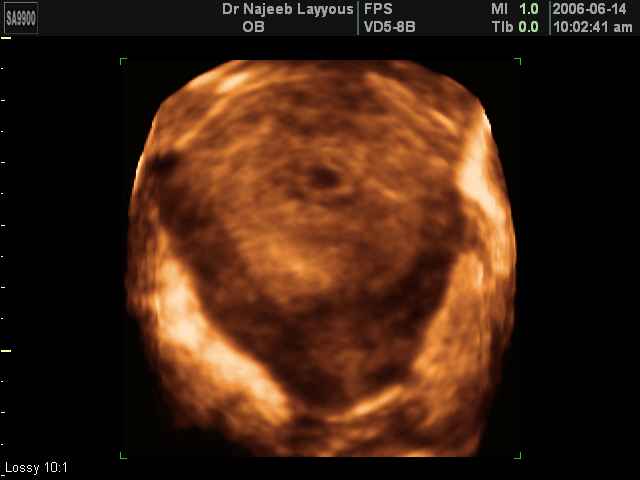

- 3D Photos Ecographie du Premier Trimestre